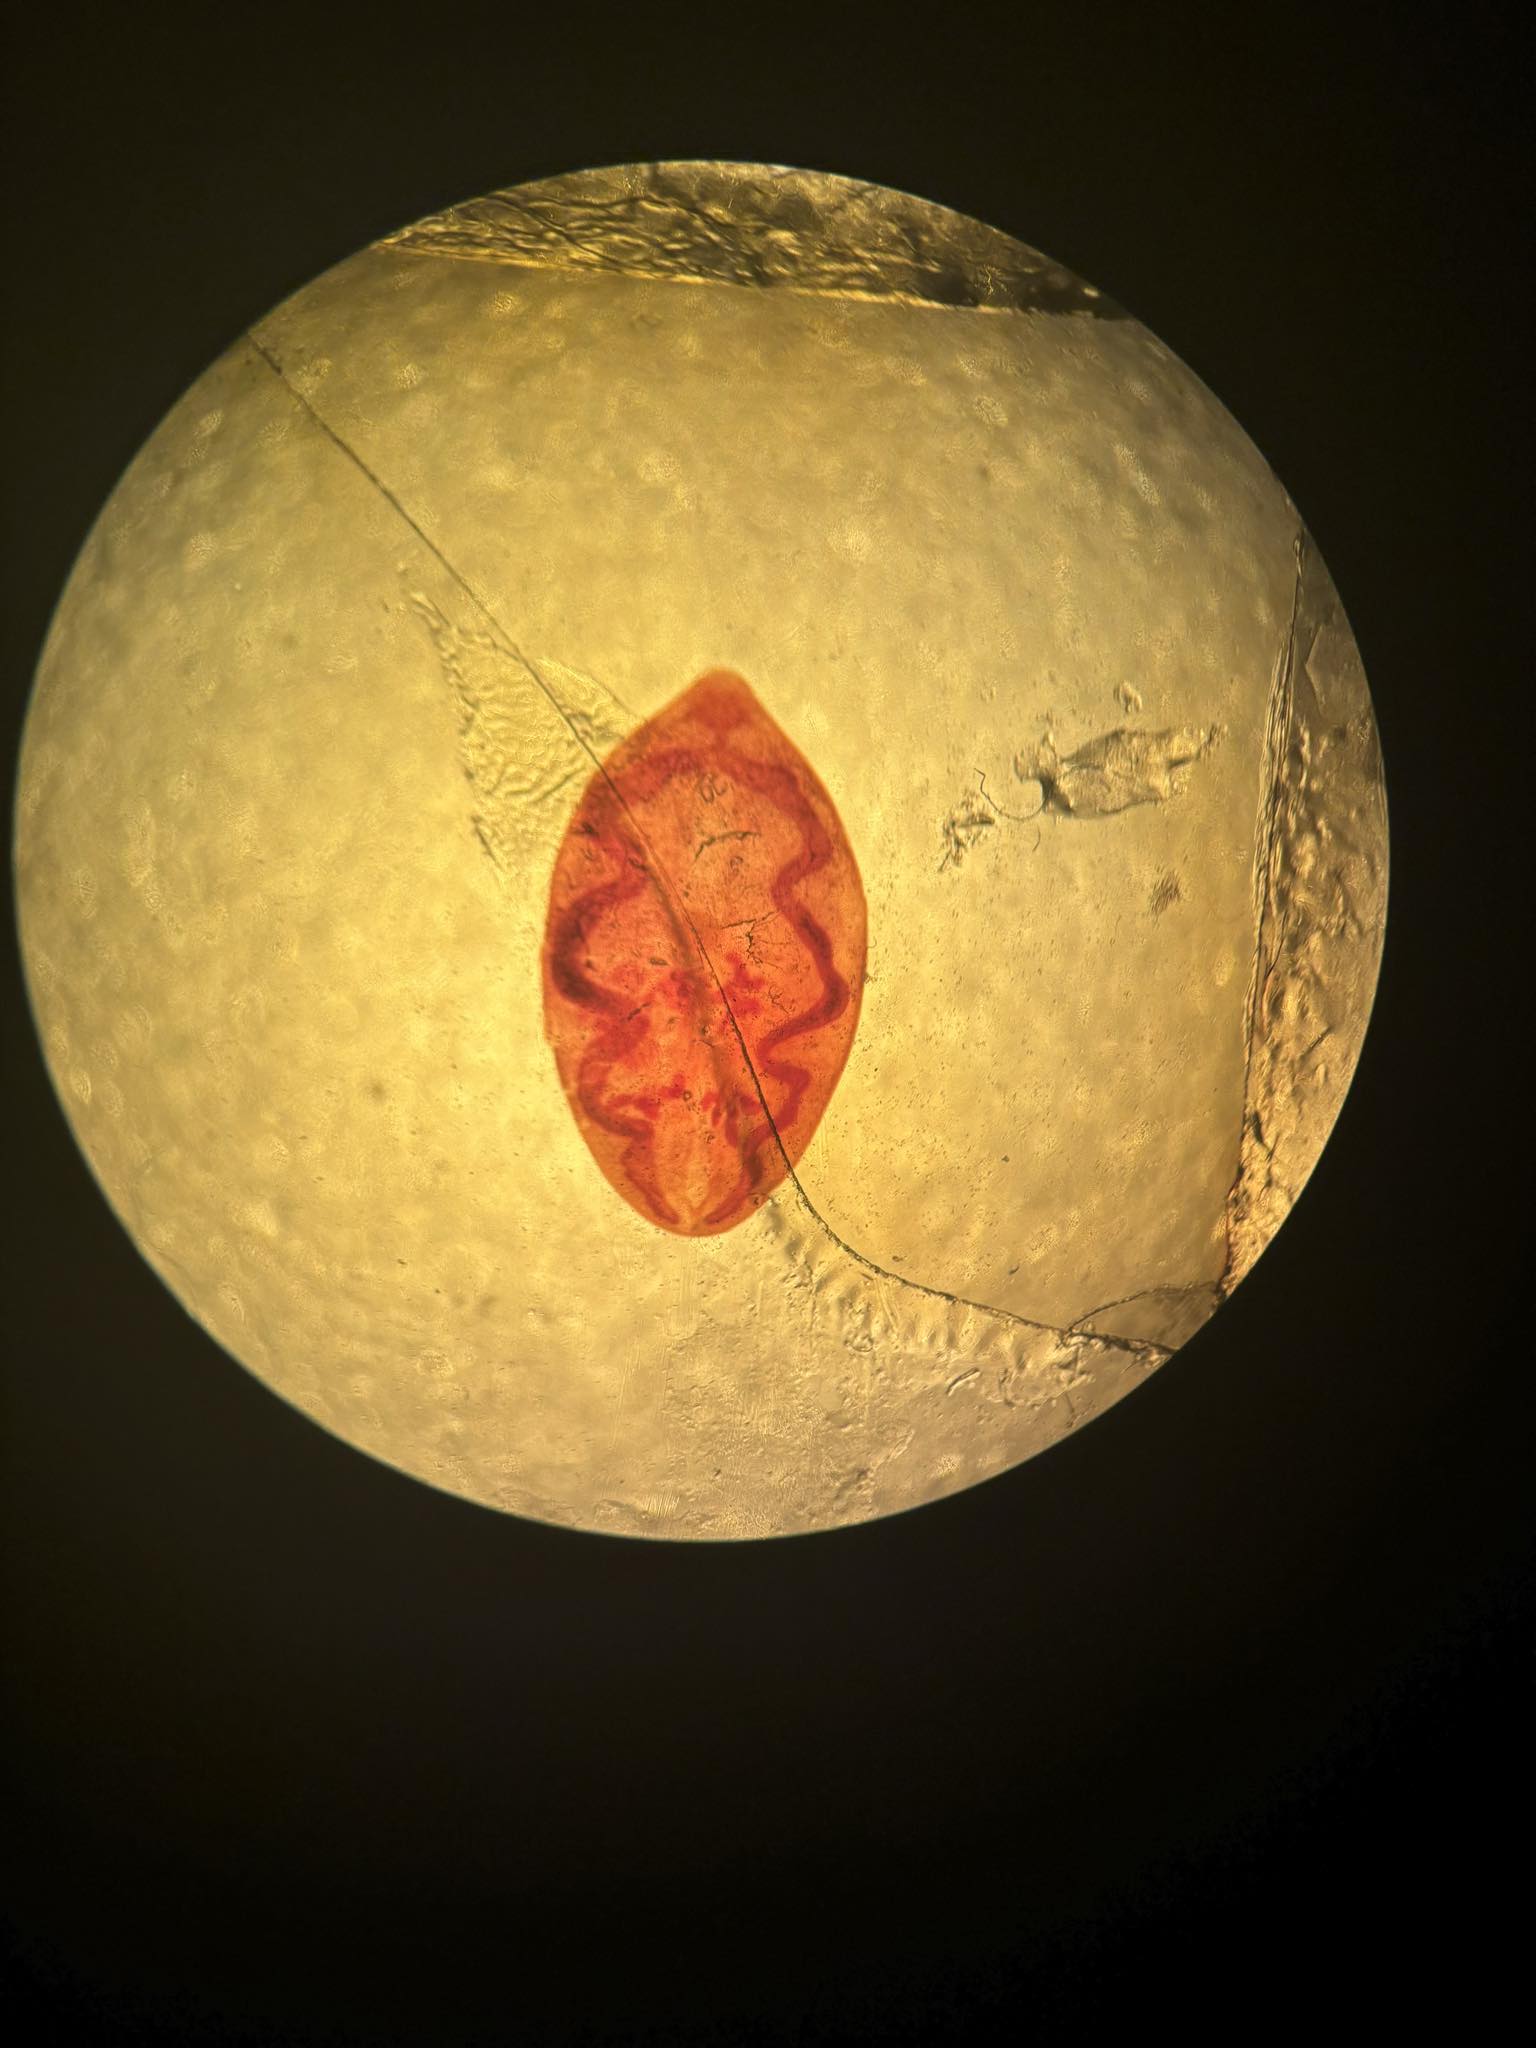

fasciola hepatica postać dojrzała

fasciolopsis buski postać dojrzała